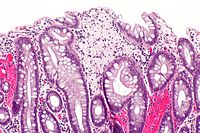

Xanthomatous polyp. H&E stain.

Xanthoma is a benign lesion due to the accumulation of lipid. It may be seen in association with hyperlipidemia.